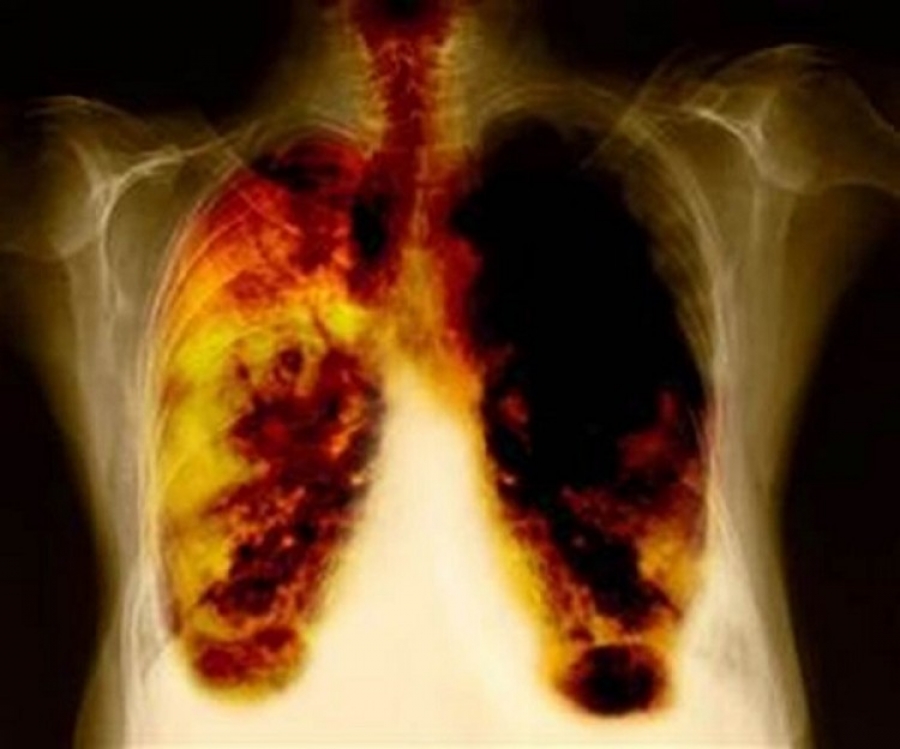

El cáncer representa uno de los mayores problemas sanitarios a nivel mundial, ya que afecta a 1 de cada 3 personas y es la causa de muerte de más de 8 millones de personas por año, más que el VIH/Sida, la malaria y la TB juntas.

En el país, este padecimiento se ha convertido en la segunda causa de muerte por tumores malignos en el hombre y la octava en mujeres, siendo la enfermedad más importante atribuible al tabaquismo.